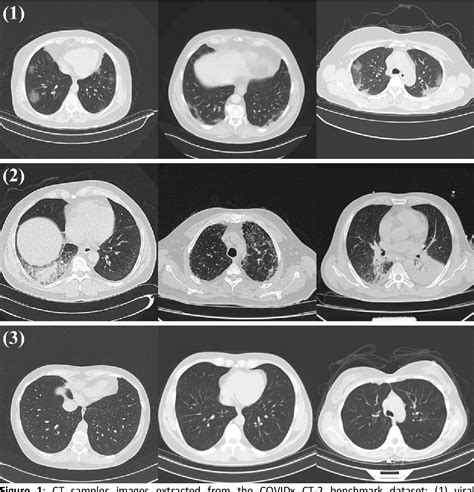

Once the scan is completed, a radiologist will interpret the images and generate a report. When viewing a Pneumonia CT Scan, medical professionals look for specific patterns of lung involvement. These patterns often indicate the type of pneumonia or the severity of the inflammatory response.

Common findings often described in reports include:

• Consolidation: This refers to the filling of air spaces (alveoli) with fluid, pus, or other material, appearing as dense, white areas on the scan.

• Ground-Glass Opacity (GGO): A hazy appearance in the lungs, indicating partial filling of air spaces or thickening of the lung interstitium. This is often seen in viral pneumonias.

• Bronchograms: The appearance of air-filled bronchi surrounded by consolidated lung tissue.

• Pleural Effusion: The buildup of fluid in the space between the lung and the chest wall.

• Nodules or Cavitation: These findings may prompt further investigation to rule out other infections or malignancy.

It is important to remember that these findings must always be correlated with the patient's symptoms, laboratory results, and clinical history. A report with "positive findings" does not always imply a worst-case scenario, as many patterns are typical of common bacterial or viral infections.